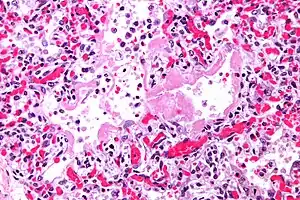

| Micrograph of diffuse alveolar damage, the histologic correlate of acute interstitial pneumonitis. H&E stain. | |

Rapid progression from initial symptoms to respiratory failure is a key feature. An X-ray that shows ARDS is necessary for diagnosis (fluid in the small air sacs (alveoli) in both lungs). In addition, a biopsy of the lung that shows organizing diffuse alveolar damage is required for diagnosis. This type of alveolar damage can be attributed to nonconcentrated and nonlocalized alveoli damage, marked alveolar septal edema with inflammatory cell infiltration, fibroblast proliferation, occasional hyaline membranes, and thickening of the alveolar walls. The septa are lined with atypical, hyperplastic type II pneumocytes, thus leading to the collapse of airspaces. Other diagnostic tests are useful in excluding other similar conditions, but history, X-ray, and biopsy are essential. These other tests may include basic blood work, blood cultures, and bronchoalveolar lavage. The clinical picture is similar to ARDS, but AIP differs from ARDS in that the cause for AIP is not known.

Acute interstitial pneumonia (AIP)/Idiopathic DAD